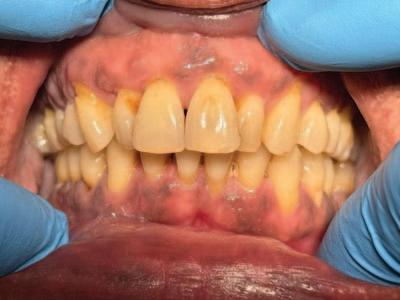

Quiz answers

1. Appearance and distribution:

n brown to dark brown, flat, diffuse areas mainly on the attached gingiva and interdental papillae;

n symmetrical pattern, more pronounced in the anterior and lower gingiva; and,

n no swelling, ulceration, or loss of surface texture.

2. Most likely cause:

n physiologic (ethnic) pigmentation due to increased melanin production by melanocytes in individuals with darker skin types; and,

n present from birth or early childhood, representing a normal genetic variation.

3. Distinguishing physiologic from pathologic pigmentation:

n physiologic pigmentation: bilateral, symmetrical, flat, present from birth, stable over time, no symptoms, no mucosal changes; and,

n pathologic pigmentation: irregular, focal, new in onset, may be associated with drugs, systemic disease, or neoplastic changes, may be symptomatic or evolving.

4. Treatment:

n no treatment required, as it is a normal, benign finding; and,

n cosmetic depigmentation (e.g., laser) may be considered for aesthetic reasons; results may vary.

5. Documentation:

n take intraoral photographs/scan for baseline record;

n record detailed clinical notes including distribution, symmetry, and any associated findings;

n review medical and medication history to rule out systemic causes; and,

n monitor for changes during routine dental visits.

6. Risk factor for periodontal disease:

n current evidence suggests that physiologic (ethnic) gingival pigmentation may be associated with an increased risk of periodontal disease, although further research is needed to determine whether this relationship is causal or influenced by confounding factors.

7. Referral

Referral to an oral medicine specialist should be considered if:

n pigmentation is new, rapidly changing, or asymmetrical;

n there is ulceration, induration, bleeding, or pain; or,

n there is suspicion of systemic disease (e.g., Addison’s disease) or drug-related pigmentation.